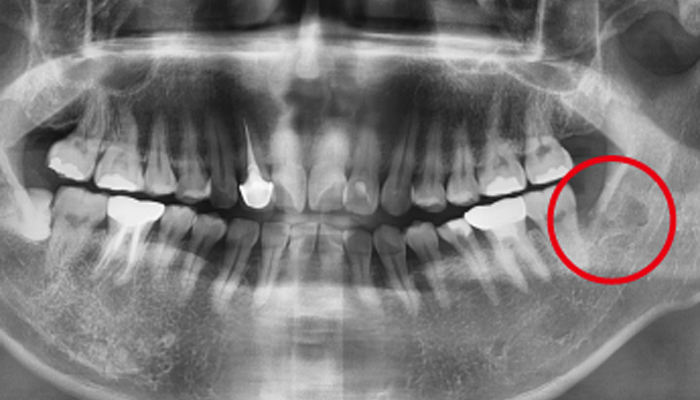

사랑니 발치 전후 사례

• 치료 전

치료 후